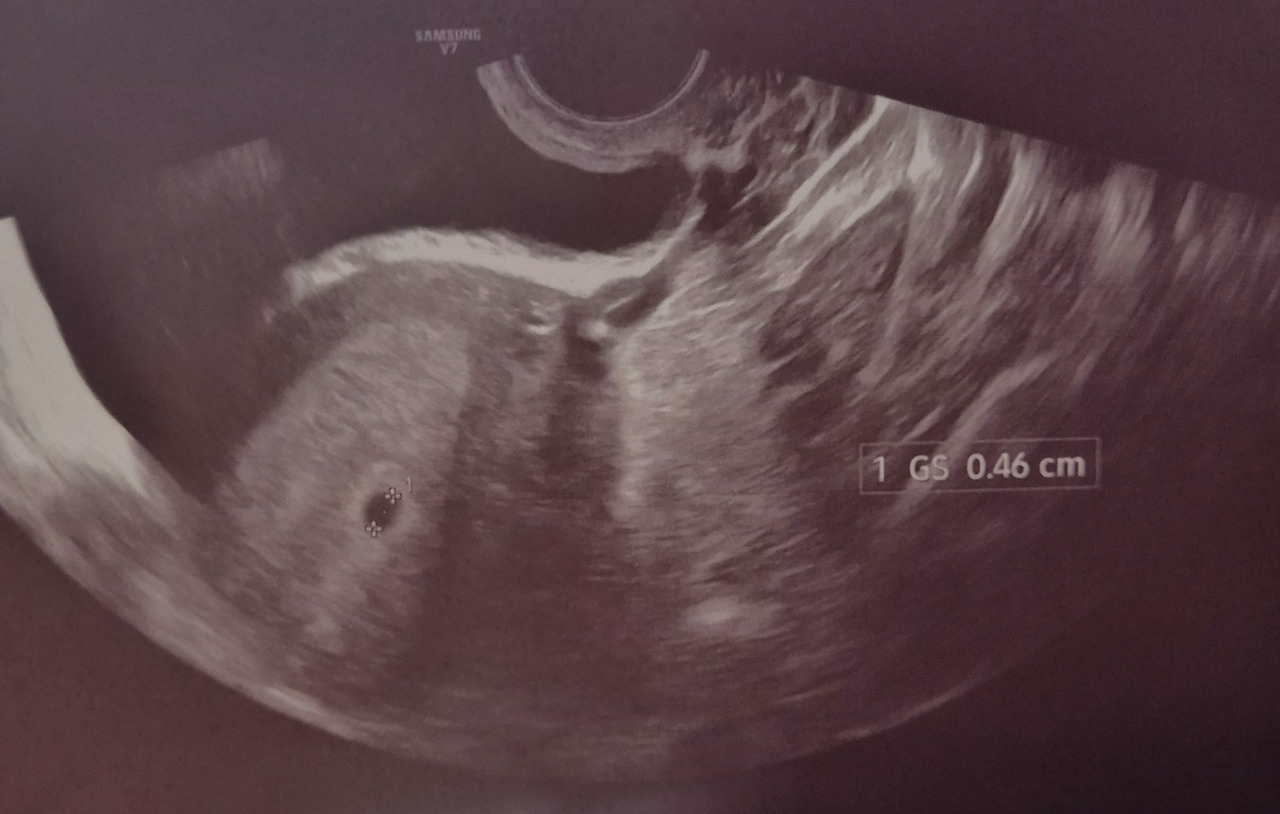

하루만 있으면 진료라 출혈도 없는데 버텨볼 만하지 않나 싶지만.. 출혈 없는 통증이었는데 유산된 경험도 있었기에..(물론 뒤늦게 피가 쏟아지긴 했었다) 불안한 마음으로 보건소에 가서 초음파를 보았는데...!!

처음 만난 우리 복복이 아가집...

안녕, 복복아 ㅎㅎㅎ

우리 아이는 내 생각보다 강했고 벌써 자신의 안식처인 아가집을 짓고 있었다

처음 아가집 확인하고 잘 자라고 있구나 아이는 괜찮겠구나.. 안심하고 그날저녁 샤부샤부 먹고 집 와서도 계속 어지러워서 아무것도 하지 않고 누워서 쉬었다.